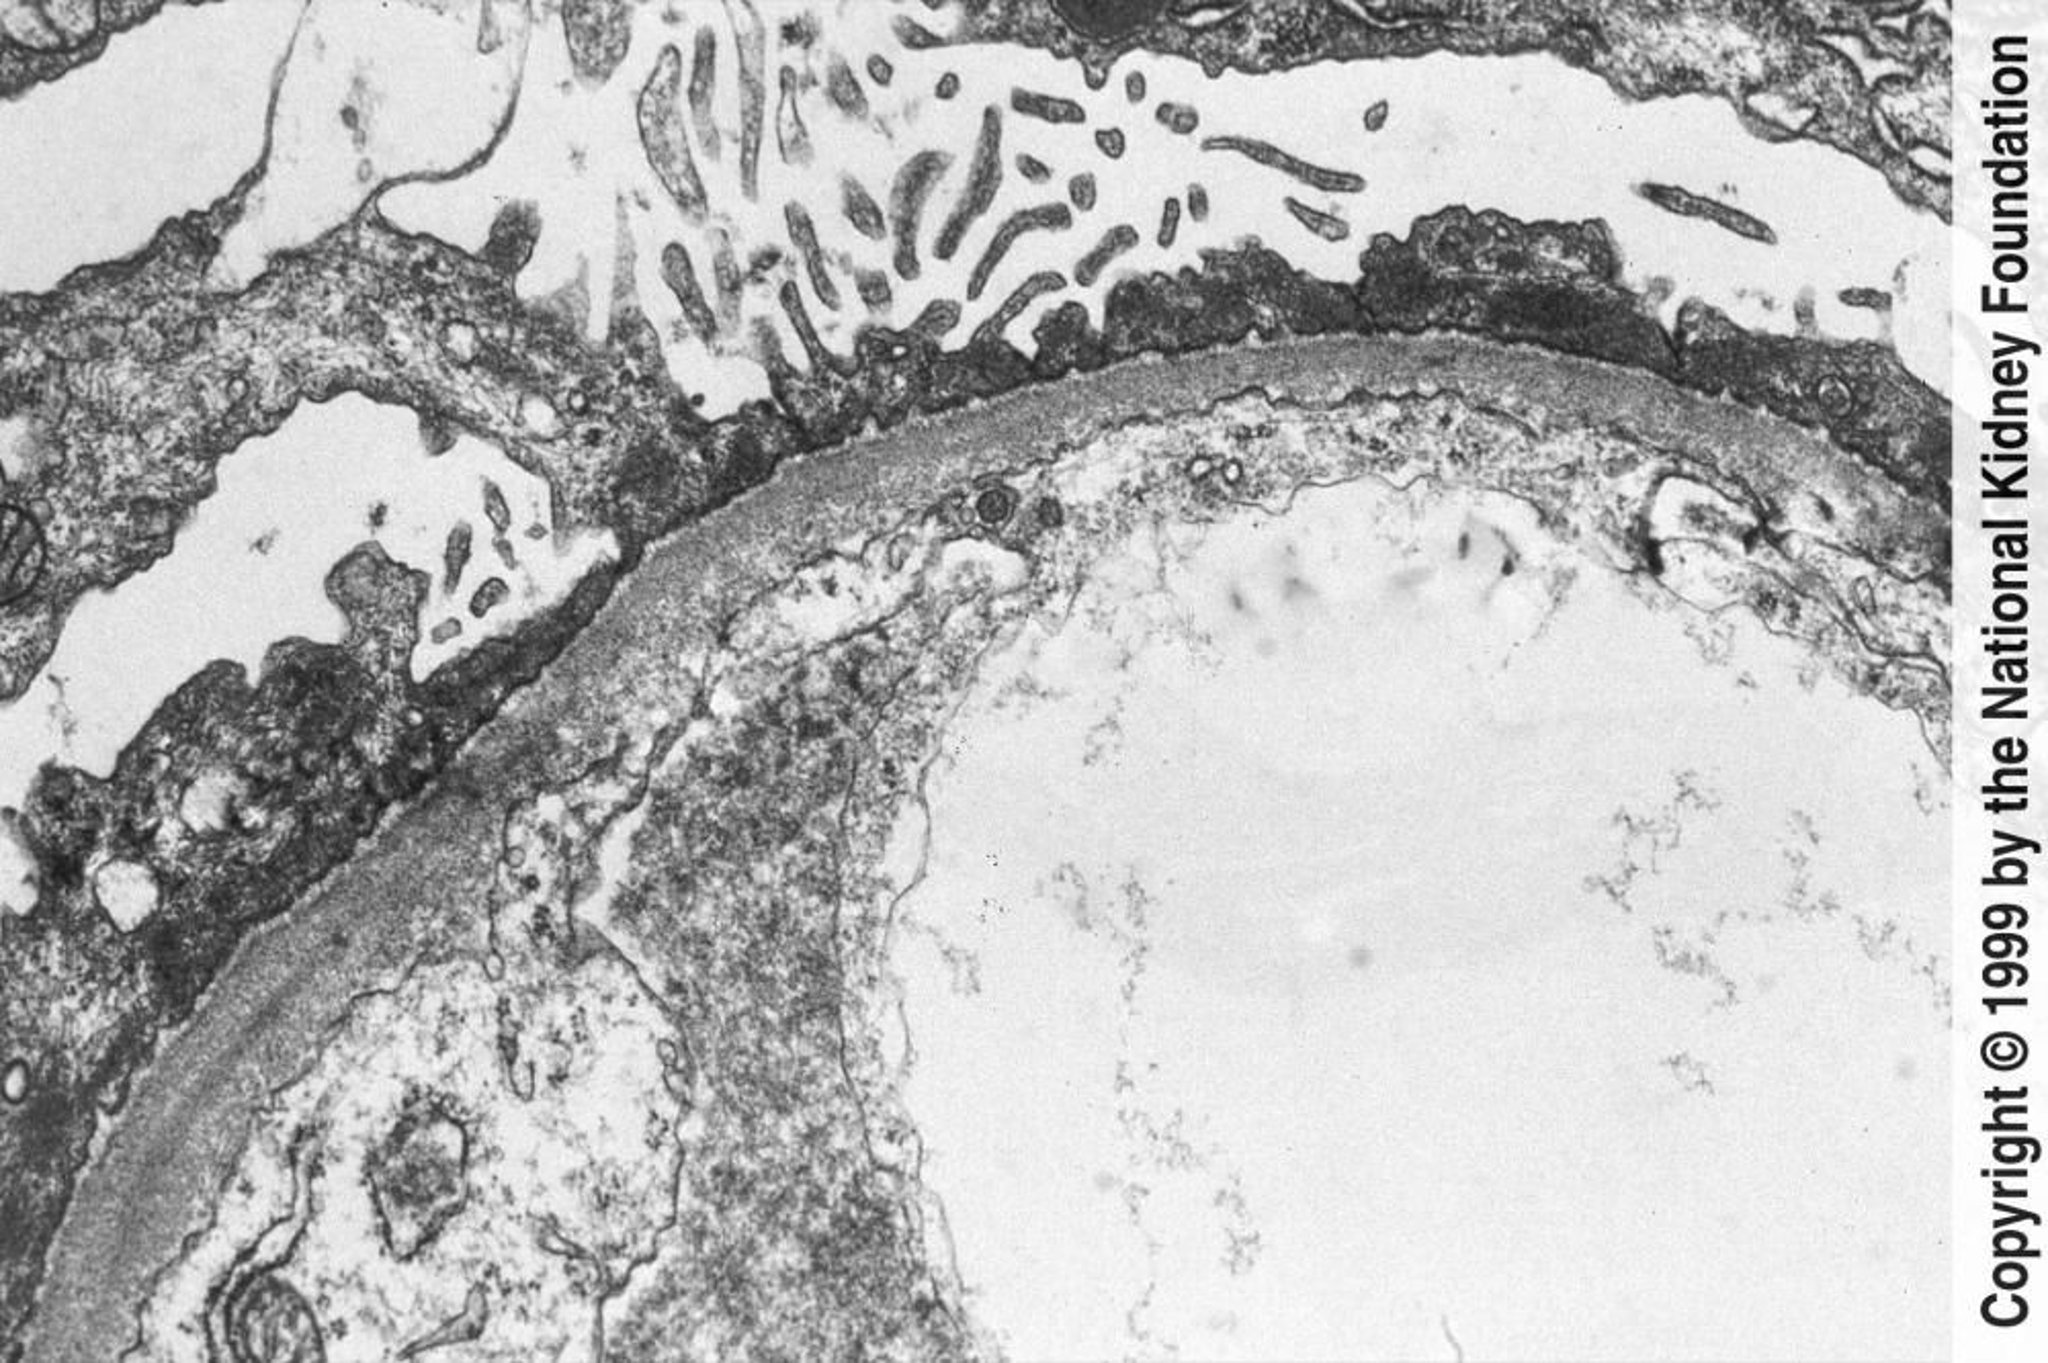

Хвороба мінімальних змін

Diffuse effacement of foot processes can be seen on transmission electron microscopy (×800).

Image provided by Agnes Fogo, MD, and the American Journal of Kidney Diseases' Atlas of Renal Pathology (see www.ajkd.org).